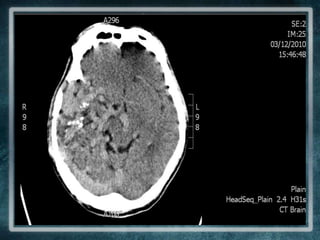

WARD: Investigation doneFull Blood Count | Liver Function Test | Glucose Level | Renal ProfileNormalCT Brain was ordered…..

MANAGEMENT IN THE WARD| Neurosurgical View | CT Brain done  Cerebral oedema and complex AVMNo surgical management available (grade 5 AVM)

AVM: SHORT OVERVIEWPatient has a right extensive fronto-temporo-occipital AVMNot curable in this caseCausing the mood symptoms and epilepsy

MANAGEMENT IN THEWARD| Neurosurgical View | CT Brain done  Cerebral oedema and complex AVMNo surgical management available (grade 5 AVM)